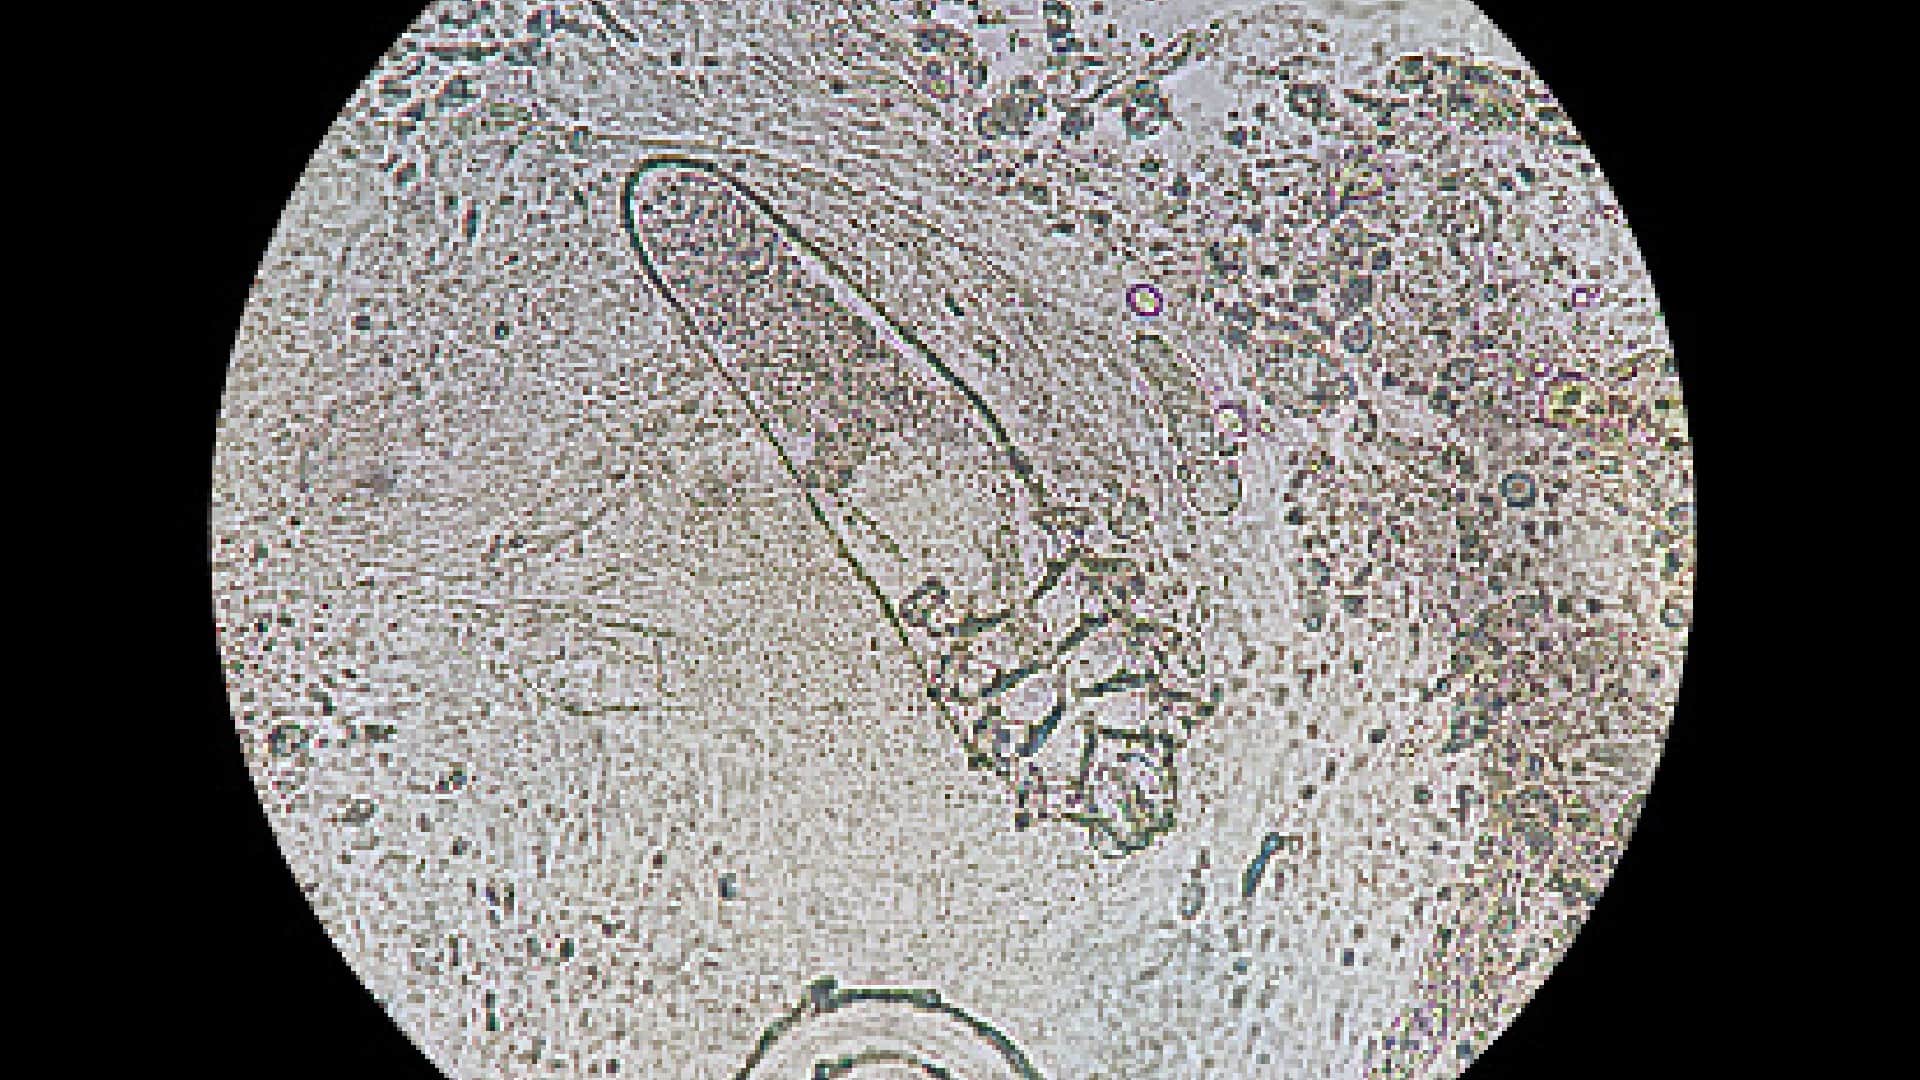

कहा जाता है मानव शरीर कुदरत का बनाया एक ऐसा करिश्मा है, जिसमें कई सारी खूबियां हैं। इसके बारे में अधिक से अधिक जानकारी प्राप्त करने के लिए वैज्ञानिक लगातार मानव शरीर पर शोध करते रहते हैं। शोध के दौरान वैज्ञानिक इंसानी शरीर के हर एक अंग के बारे में जानकारी प्राप्त करने की कोशिश करते हैं। खून से लेकर यूरिन की जांच के जरिए शरीर में होने वाली बीमारियों के बारे में पता चलता है। वहीं अगर शरीर की रोग प्रतिरोधक क्षमता कमजोर होती है, तो बैक्टीरिया और वायरस भी इंसान को बीमार बना सकते हैं। इसी तरह हमारी त्वचा में संक्रमण और डेड स्किन के बारे में बात की जाए तो इनसे जुड़ी कुछ ऐसी बातें हैं, जिनके बारे में हमें पता भी नहीं होता है। आज हम आपको हमारी त्वचा पर पल रहे ऐसे जीव के बारे बताने जा रहे हैं, जिनके बारे में जानकर आप हैरान रह जाएंगे।

Tiny Mites: सोते समय ये जीव इंसानों के चेहरे पर परिवार बढ़ाने का करते हैं काम, स्टडी में दावा